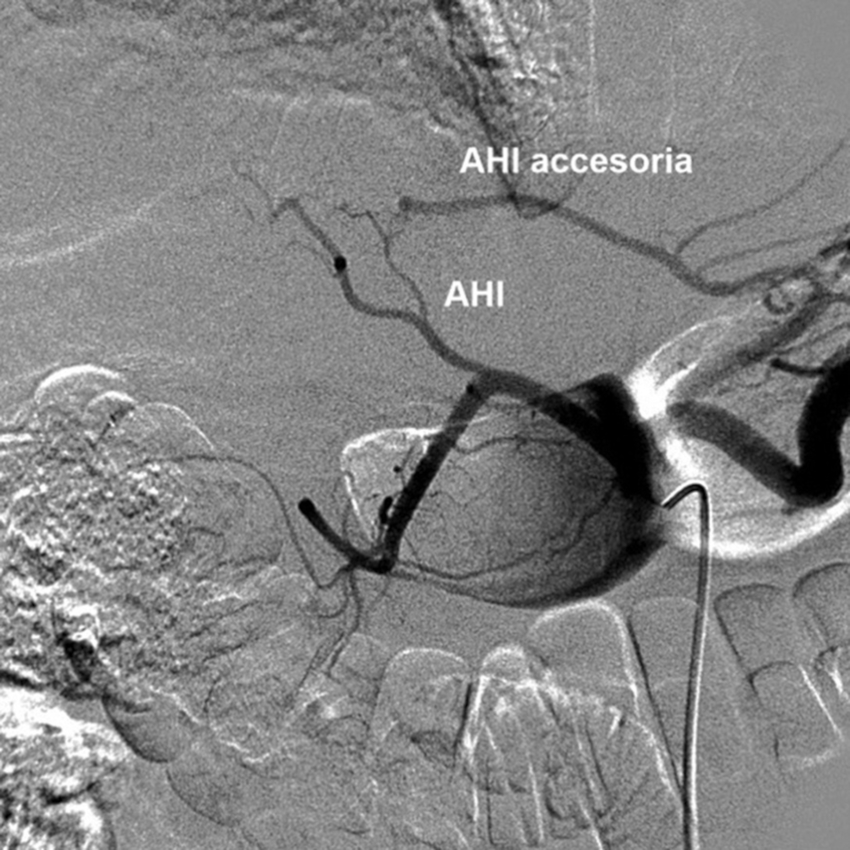

Tipo 2: AHD con origen en la AHC. AHI aberrante con origen en la AGI (Fig. 5).

Tipo 5: AHD y AHI con origen en la AHC. AHI accesoria desde la AGI (Fig. 10).

Tipo 7: AHD y AHI con origen en la AHC. AHD accesoria desde la AMS y AHI accesoria desde la AGI (Figs. 13 y 14).